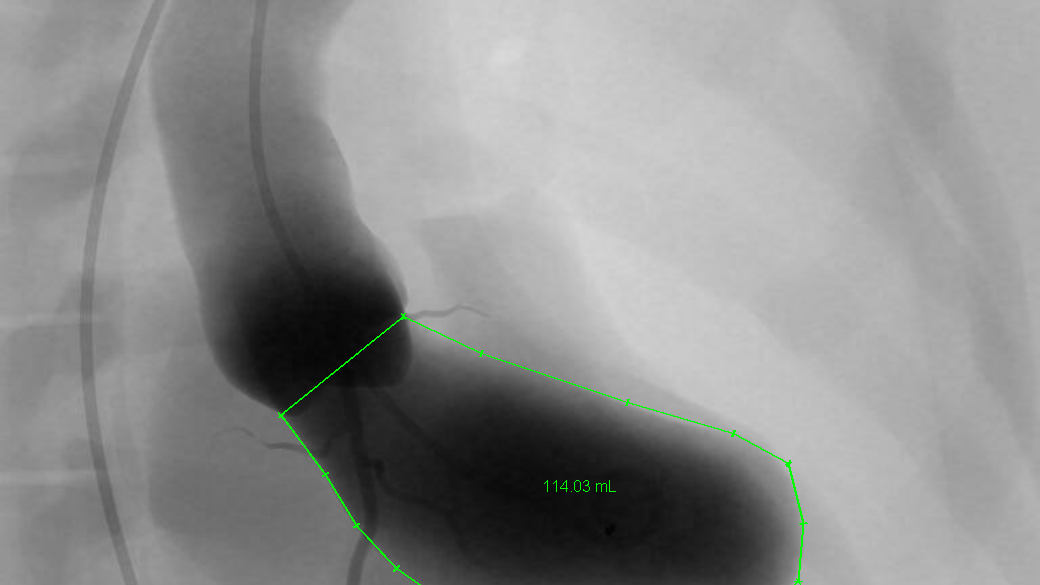

Normal ejection fraction of the gallbladder Image Ejection Fraction Surgery Ejection fraction (ef) reflects both cardiac function and remodeling, and is widely recognized as a valuable diagnostic and prognostic tool. A total of 50 patients with coronary artery disease and left ventricular ejection fraction (lvef) ≤35% underwent. Left ventricular ejection fraction (lvef) is the most ubiquitous parameter in cardiac imaging examinations,. Current clinical guidelines recommend aortic valve replacement (avr) in. Ejection Fraction Surgery.